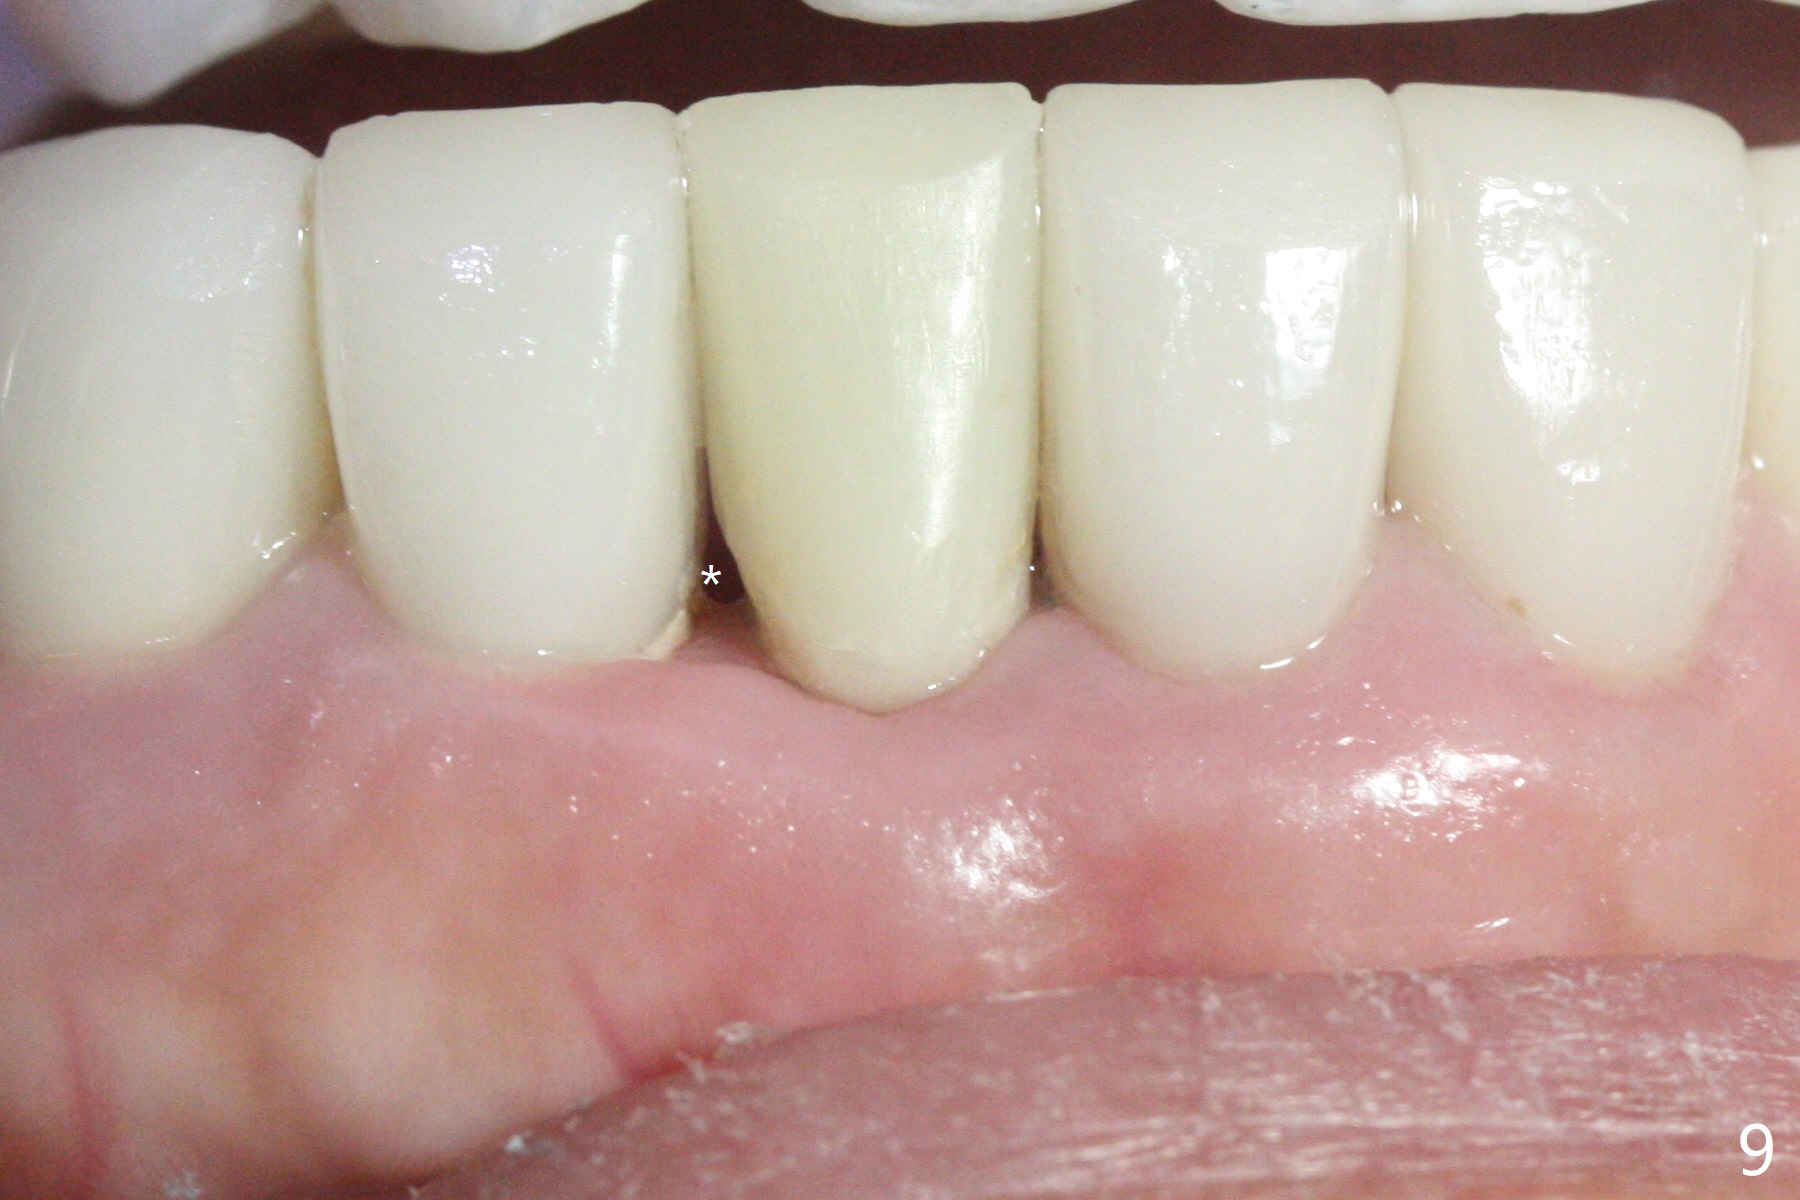

A drawback of implant planning at #25 is not to use a preop PA (Fig.1 (^ fracture line)). The initial trajectory seems to be alright (Fig.2), but a 2.5x14(2) mm implant placed is close to the tooth #26 (Fig.3). In fact the affected tooth is deviated distal; osteotomy should be initiated in the mesial slope of the socket (Fig.4 red line). The final trajectory appears to be perfect (Fig.5). Furthermore the 1st intraop PA should be analyzed carefully (Fig.6). A new osteotomy should be established mesial or the existing one should be moved mesial with Lindamann bur (Fig.7). The distal implant placement may be related to more bone loss in the distal crest 3.5 months postop (Fig.8) and more severe distal papillary recession (Fig.9 *). The bone density increases at the levels of the non-thread and thread portions of the implant (in the original socket) nearly 10 months post cementation (Fig.11 *, <). There is no bone loss 16 months post cementation (Fig.12).